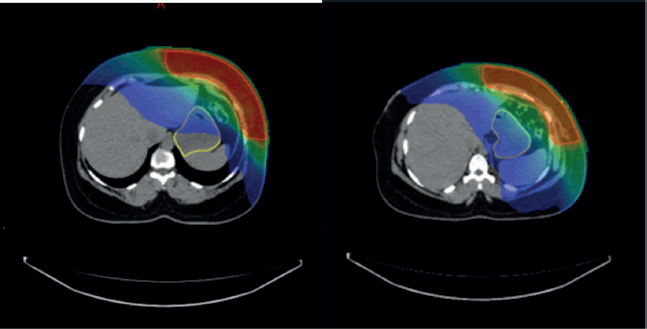

Overall, the significant factors influencing acute upper GI toxicity included radiation technique, RT dose and dose to stomach (D10 cc, D30 cc and D60 cc). Importantly, left chest wall or breast irradiation with or without RNI during FB was associated with a significantly higher risk of GI toxicity compared to DIBH, which holds a significant negative correlation implying a protective effect and helps in reducing GI toxicity (p = 0.035) (Supplementary

Figures 1a,b and 2a,b). Additionally, a positive correlation was found between larger PTV volume and the risk of developing acute upper GI toxicity (p = 0.036).

The Mann-Whitney U test was used to compare stomach dose parameters (D10, D30 and D60 cc) between FB and DIBH. Stomach D10 cc, the higher-dose region most closely associated with acute toxicity, showed no significant difference between FB and DIBH (Mann-Whitney U = 898.500, Z = −1.712, p = 0.087). This suggests that DIBH helps control the dose to critical stomach sub-volumes, potentially reducing the risk of upper GI toxicity. Interestingly, D30 and D60 cc doses were higher in the DIBH group (p = 0.013 and p = 0.002, respectively). However, these differences are likely to reflect anatomical and positional variations associated with breath-hold techniques rather than an increased clinical risk. Clinical correlation with upper GI toxicity indicated a protective trend for DIBH, reinforcing its role in mitigating toxicity by improving treatment reproducibility and reducing motion-related dose variability (Supplementary Figure 2a and b).

Supplementary Figure 1. (a and b): Axial CT scan showing stomach position in FB (VMAT Technique), Figure 3b: showing stomach position in DIBH (VMAT Technique).